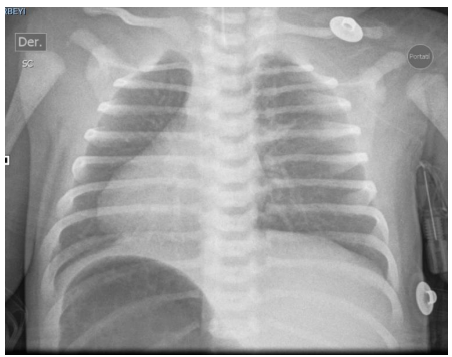

Newborn female referred from San Vicente de Paul Hospital for respiratory distress syndrome and suspected congenital heart disease, this is a 1 day old newborn, the result of the fifth pregnancy, a 41 year old mother, 39 weeks gestation, Grava 5, 2 stillbirths, prenatal check-ups number 5, blood type O positive, mother has gestational diabetes, perinatal screening: HIV negative, VDRL non-reactive, Hepatitis B negative, Toxoplasma IGG positive and IGM negative, delivered by cesarean section due to iterative, born with the following anthropometric parameters: weight 3520 grams, height 50 cm, head circumference 36 cm, chest circumference 35 cm. Spontaneous neonatal adaptation, Apgar 8 - 10 - 10, at birth the baby develops respiratory distress syndrome with a 3-point Silverman - Anderson score, for which reason they are transferred to the newborn unit, non-invasive ventilation is started, a chest x-ray is taken where dextrocardia is evident, for which reason they are referred to the UROS Clinic for comprehensive management in the neonatal intensive care unit. On admission, the patient was hemodynamically stable and showed no signs of low output. He received noninvasive ventilatory support with a high-flow nasal cannula, a FIO2 of 35%, with saturation at target levels. However, during hospitalization, the patient's respiratory condition deteriorated with increased effort, increased retraction, and thoracoabdominal dissociation. Therefore, orotracheal intubation was performed with a 3.5 tube, which was 10 cm from the commissure. Ventilation parameters were adjusted. The patient's progress was favorable. Venous blood gases were taken and showed a pH of 7.32, PO2 35, PCO2 43, HCO3 22, BE -3.9, and lactate of 4.1 with normal serum electrolytes. A chest x-ray was taken and showed a cardiac silhouette on the right and a liver on the left. He ventilated 9 intercostal spaces. without opacities, diagnosis situs inversus totalis , hemodynamically well perfused without low output with blood pressure and heart rate at goals, without indication of inotropic support, heart sounds audible on the right. pulses present. Complementary studies are performed CENTRAL NERVOUS SYSTEM ULTRASOUND study within normal limits, TOTAL ABDOMEN ULTRASOUND An alteration in the position of the abdominal organs is striking, observing the spleen in the right hypochondrium and the liver in the left hypochondrium. Liver of normal shape, size and echogenicity, without focal or diffuse lesions in its parenchyma. Gallbladder and bile duct without alterations. Kidneys, spleen, pancreas and retroperitoneum of normal ultrasound appearance. Empty bladder which prevents assessment of pelvic organs. No masses, collections or free fluid are identified in the abdominal cavity. OPINION: ALTERATION IN THE POSITION OF ABDOMINAL ORGANS (SPLEEN AND LIVER) AN ECHOCARDIOGRAM IS SUGGESTED TO RULE OUT DEXTROCARDIA, ECHOCARDIOGRAM by pediatric cardiology showing CONSERVED SYSTODIASTOLIC FUNCTION OF THE LEFT VENTRICLE TAPSE 9 MM TRICUSPID AND PULMONARY FAILURE PHYSIOLOGICAL OVALE FOSSA 4.1 MM PSPE 34.7 MMHG RESTRICTIVE DUCTUS TOWARDS CLOSURE, DEXTROCARDIA, multidisciplinary evaluations are performed GENETICS patient in stable general condition situs inversus totalis is an alteration that occurs in about 1:10,000 people, with a higher prevalence in men than in women. It is important to rule out whether this occurs in isolation or as part of a more complex syndrome. It is important to keep in mind that 80% of patients have heart disease, which is why a transthoracic echo is required to rule out any anomaly of this type. Additionally, it is important to rule out primary ciliary dyskinesia due to the history of respiratory failure reported by the service. A karyotype with G banding is requested, genomic hybridization is requested (study of deletions and duplications) PEDIATRIC NEUROLOGY patient with high neurological risk due to congenital malformation, with neurological examination with deficit for gestational age, weak suction for gestational age, with echo of the central nervous system without pathological alterations, I request a CEREBRAL MRI Clinical information: situs inversus. Findings: The myelination pattern is normal for the age. The signal from the brain parenchyma does not show alterations. Gray nuclei of the base and thalami without alterations. Subarachnoid space and ventricular system within normal limits for the age. Hypothalamic-pituitary axis, pineal region and corpus callosum of normal appearance. Structures of the posterior fossa without findings of pathological value. Preserved craniovertebral junction. Significant bilateral Oto mastoid occupation. Mucosal thickening in the pneumatized paranasal cavities. Conclusion: Significant bilateral Otomastoid occupation . Intracranial structures within normal limits for age. PEDIATRIC PULMONOLOGY chest x-ray situs inversus, without air leak, adequate lung expansion, OTORHINOLARYNGOLOGY patient with suspected immotile cilia syndrome, currently stable, an electron microscopy of the nasal mucosa is ordered, which can be performed on an outpatient basis, should continue with periodic check-ups by otorhinolaryngology, PEDIATRIC OPHTHALMOLOGY patient with no alterations in the ophthalmological examination, is considered within normal parameters. Control in 6 months , PEDIATRIC CARDIOLOGY newborn with dx of total situs inversus , the echocardiogram showed a systolic pulmonary pressure of 35 mmHg and a restrictive ductus, heart in dextrocardia without dyspnea or cyanosis, finally the patient shows favorable evolution, it is possible to withdraw respiratory support, outpatient follow-up is ordered by different specialties.

Figure 2 . G banding karyotype / Normal result 46 XX